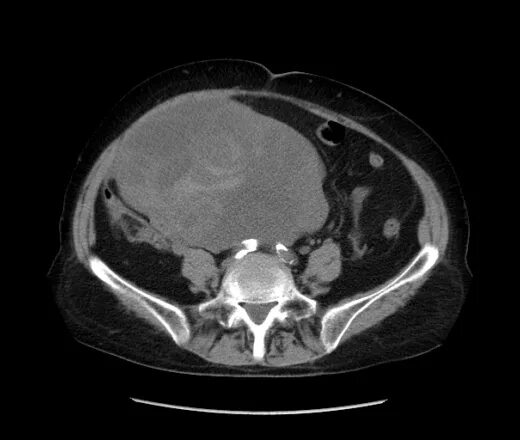

Солидные образования малый таз